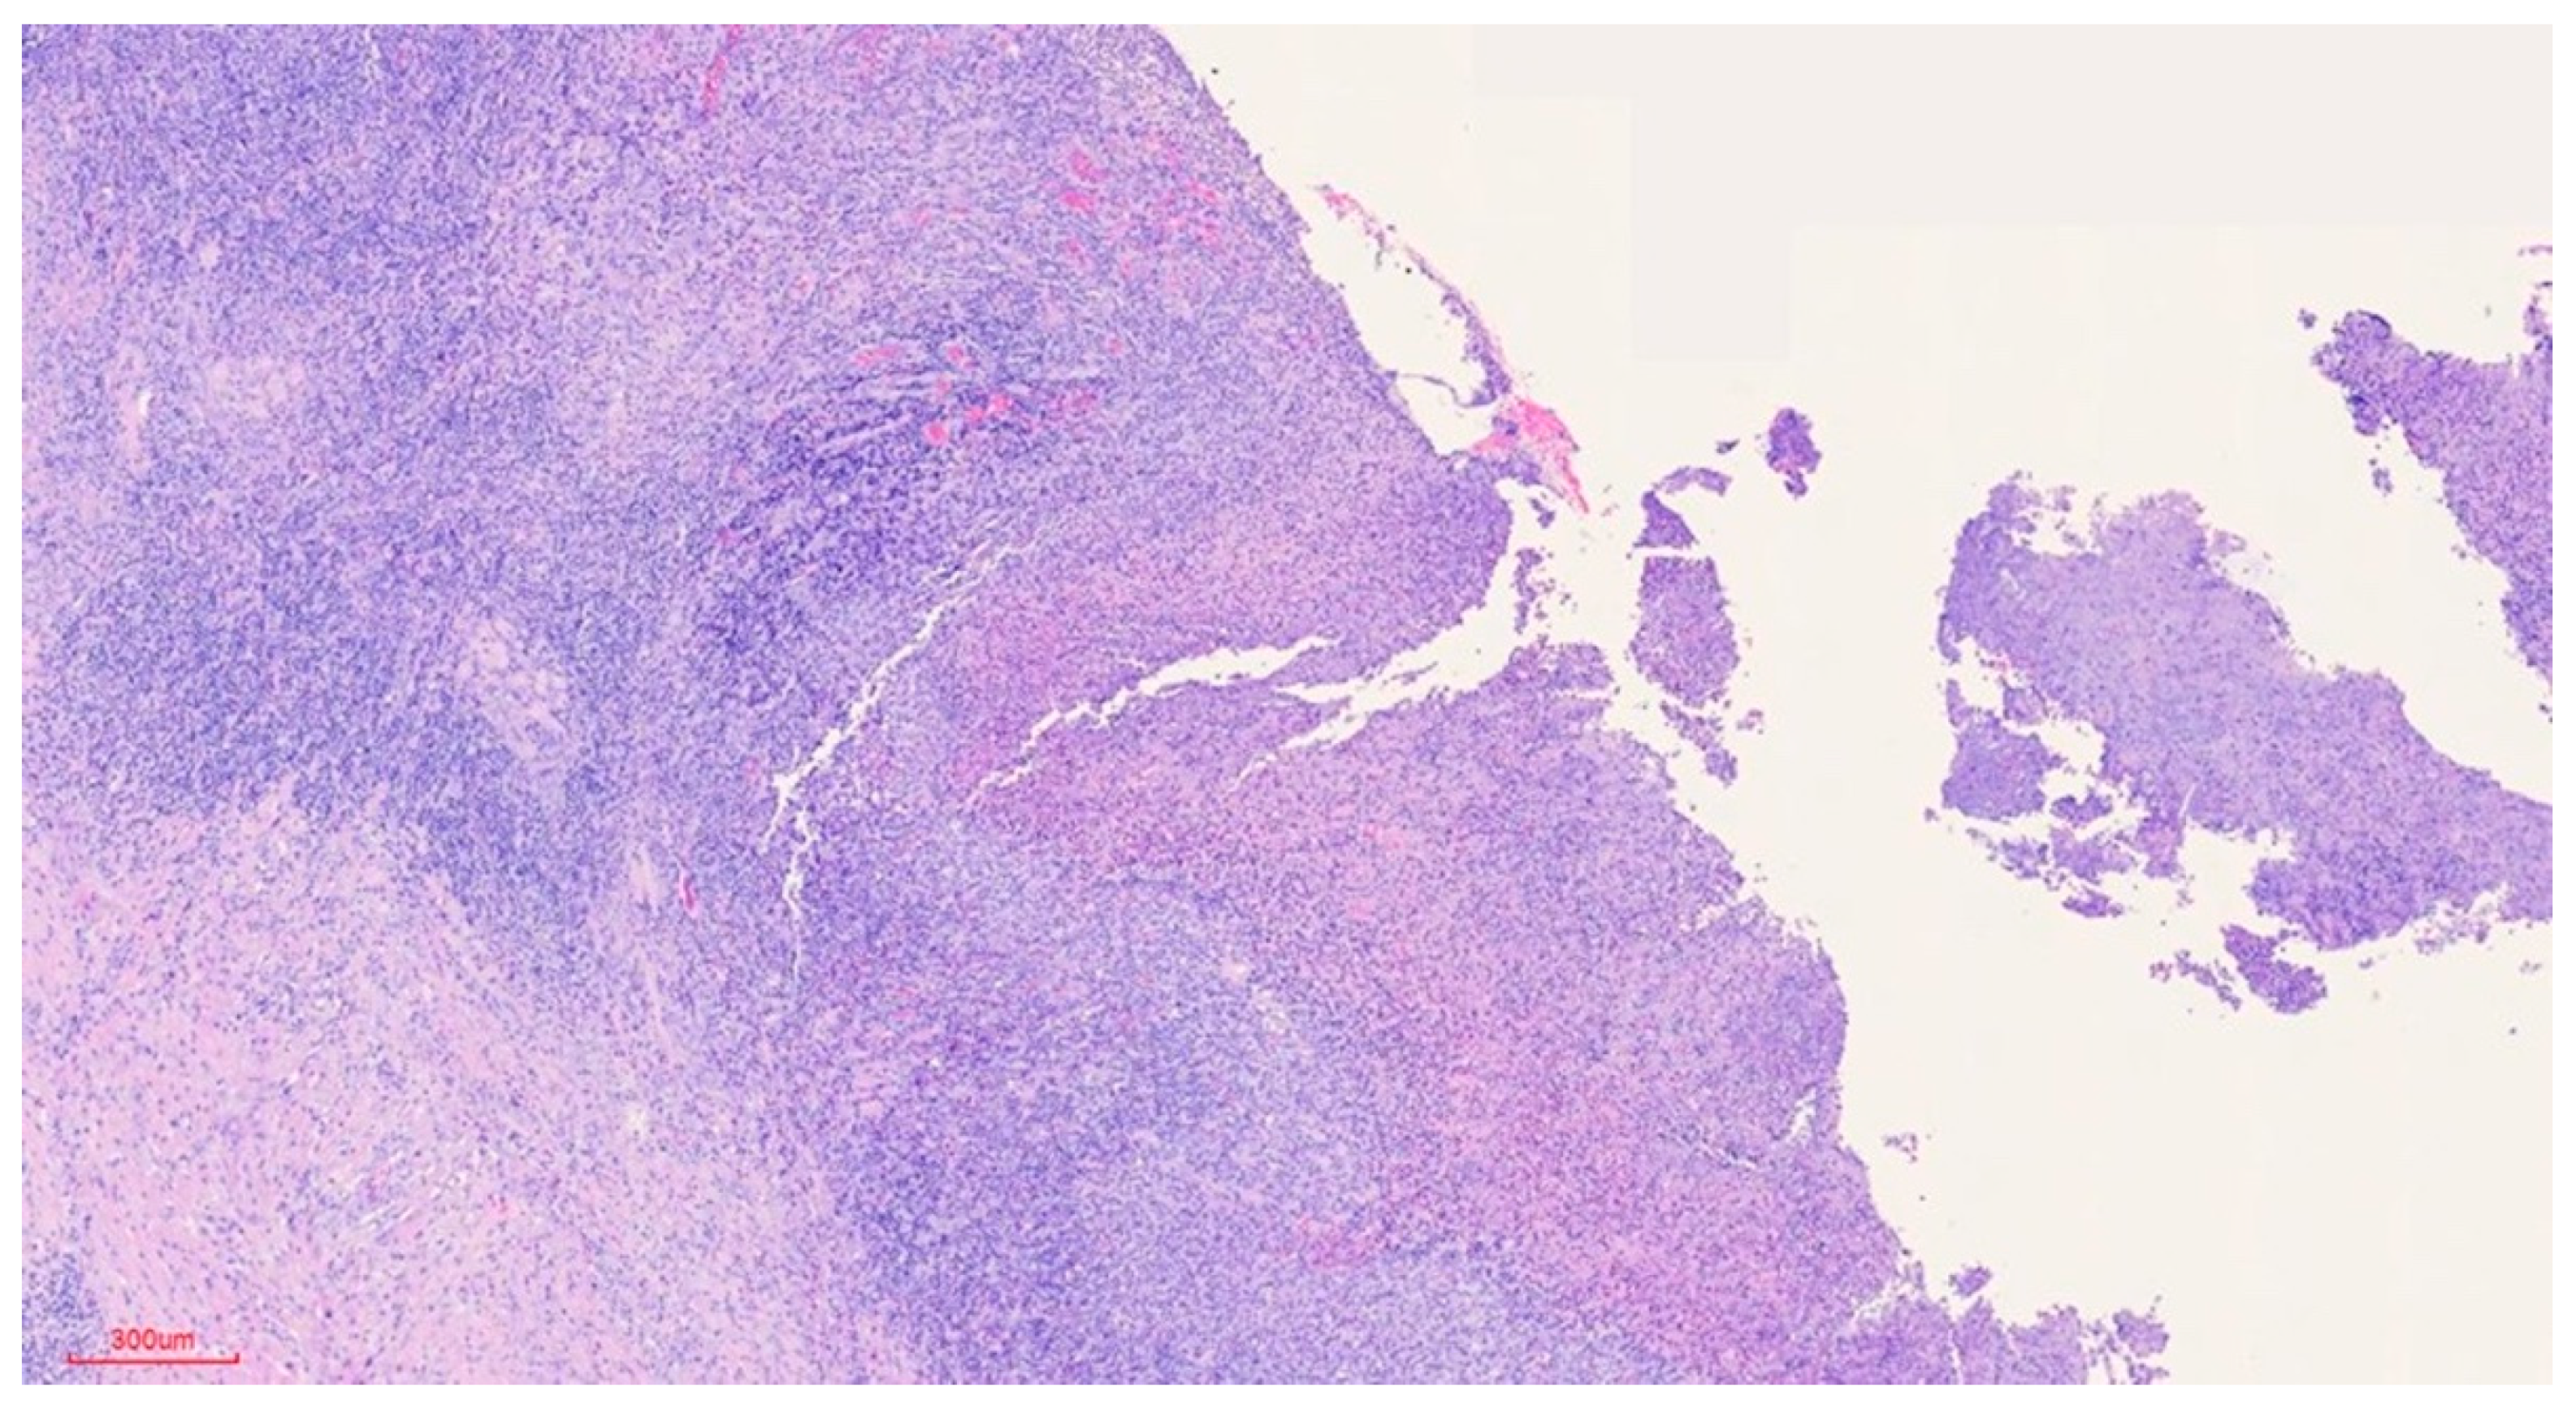

Clinically, the lesion usually has a raised hyperkeratotic border and microscopically it is characterised by a dense infiltrate of T and B lymphocytes, macrophages and mainly eosinophils24 and a tendency to penetrate the underlying muscle.

The histopathological study was resolved as follows:

a) Macroscopic description: 1.3x2 cm round fragment with 1.2 cm ulcer with raised edges and granular central area. Two samples are submitted, one from the central area and one from the periphery.

b) Microscopic findings: infiltrative ulcerative lesion covered with necrotic-fibrinoid material and consisting of an abundant polymorphous inflammatory infiltrate extending in depth around the seromucinous glands and dissociating the muscle fibres. It consists of cells of histiocytic type, lymphocytes, polynuclear neutrophils and abundant eosinophils. PAS and Grocott stains show no fungal elements. No signs of malignancy are observed (see Figures 4–9).

c) Histopathological diagnosis: histological aspect compatible with traumatic ulcerative granuloma with stromal eosinophilia.